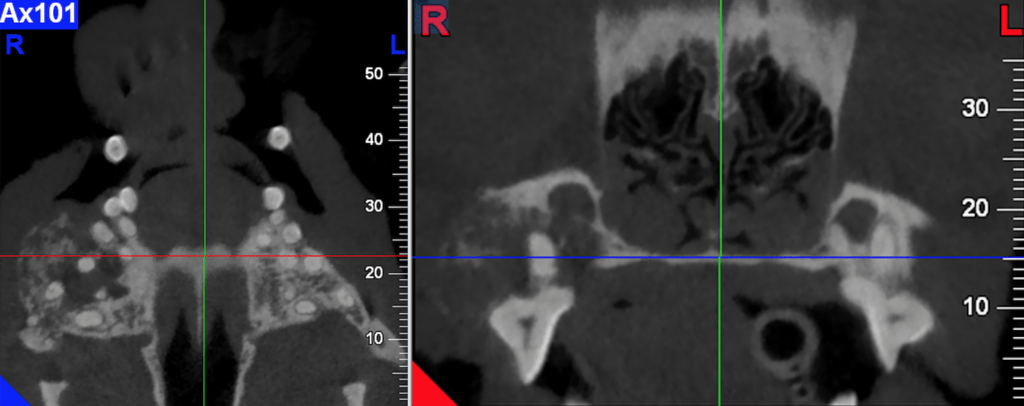

L’examen Scanner ou CBCT est le complément indissociable au diagnostic final. L’objectif est d’optimiser la localisation des marges chirurgicales et par extension le pronostic thérapeutique.

La technologie Cône beam CT offre une meilleure définition que celle du scanner. Elle sera préférée à celui-ci dans le cadre des tumeurs d’origine dentaire ou des tumeurs malignes présentant peu ou pas d’effraction faciale concomitante. Le scanner a pour avantage une analyse des contrastes qui optimise l’information au niveau des tissus mous périphériques, ganglions loco régionaux et thorax. L’Irm n’est pas la technique d’imagerie recommandée en maxillo facial considérant la durée de l’examen, son coût et surtout ses limites quant à l’interprétation des segments dento maxillaires.

Figue 1. Améloblastome maxillaire chez un chien avec lyse osseuse, imagerie en CBCT.